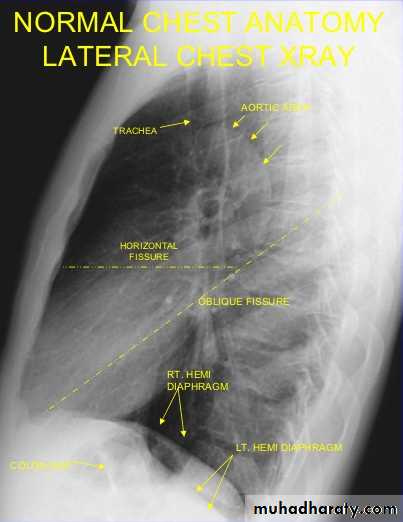

The fissures can only be seen if they lie along the line of X ray beam.

Usually only horizontal fissure, minor fissure, visible in frontal projection, while oblique, major, fissure only seen on lateral view.

On lateral view: reliable feature is that as go down the thoracic vertebral bodies, each verteb. Body app. More lucent than above till reaching the diaphragm.